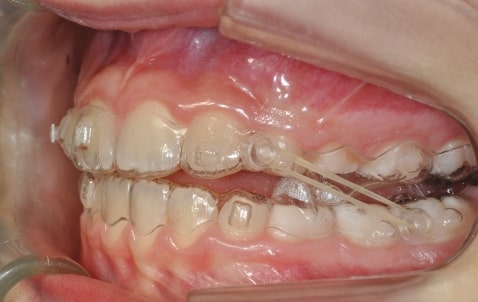

Malocclusion A6 Correction of Mandibular Retrusion in Growth phase patient | Skeletal Class II | Class II Division 1 malocclusion | Deep bite | Mixed dentition

Initial Photos and datas

Clinical examination and diagnosis

SKELETAL PATERN: Class 2

DENTAL:

- Molar and Canine class 2 on the right side – Molar and Canine clss 1 on the left side

- Increased Overjet

- DeepBite

- Mandibular Advancement (A6 protocol) + angelBuon for Class 2 Elastics (Night Time)